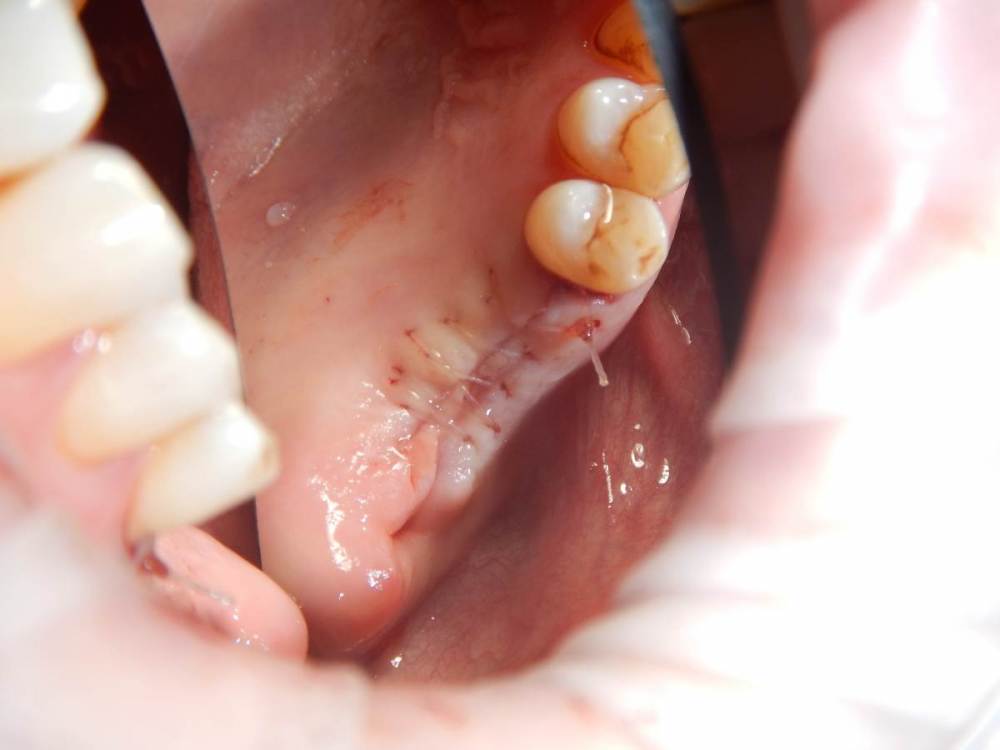

annda Опубликовано 11 июня, 2021 Поделиться Опубликовано 11 июня, 2021 (изменено) Ничего не беспокоит.Зубы удалены лет 15 назад Изменено 11 июня, 2021 пользователем annda 1 Ссылка на комментарий

Карен Аванесов Опубликовано 11 июня, 2021 Поделиться Опубликовано 11 июня, 2021 Анна здравствуйте. Версий много, вскрытие покажет, главное нет признаков воспаление, в любом случае интересный клинический случай под минимальное вмешательство, обязательно покажите развязку. 1 Ссылка на комментарий

Astronaft Опубликовано 11 июня, 2021 Поделиться Опубликовано 11 июня, 2021 Радиография была один в один с вашим случаем. Результат биопсии: рецидуальная киста с кристаллами холестерина. Но конечно может быть что-нибудь другое. 4 Ссылка на комментарий

annda Опубликовано 12 июня, 2021 Автор Поделиться Опубликовано 12 июня, 2021 (изменено) Спасибо всем. Вмешательства не было, кроме удаления. Я так понимаю, тактика заключается в доступе и банально кюретаже? Графт по убеждениям, дефект все одно получается практически четырехстеночный... Главное, не наджабить кортикалку ГП. Я так понимаю, процесс все же из пазухи, был с зубами связан? Изменено 12 июня, 2021 пользователем annda Ссылка на комментарий

Astronaft Опубликовано 12 июня, 2021 Поделиться Опубликовано 12 июня, 2021 (изменено) В моем случае процесс одонтогенный. Киста это остаток после удаления зуба. В вашем случае не должен быть из пазухи. Да - там есть истончение кортикальной пластины в одном месте, но вроде как без инвагинации. Границы везде четкие, т.е. процесс доброкачественный. Из пазухи в кость можно проникнуть только инвазивно. Лизис, а не раздвигание. Карцинома - границы были бы другие. Т.е. процесс либо происходит из самой кости, или одонтогенный. Изменено 12 июня, 2021 пользователем Astronaft 1 Ссылка на комментарий